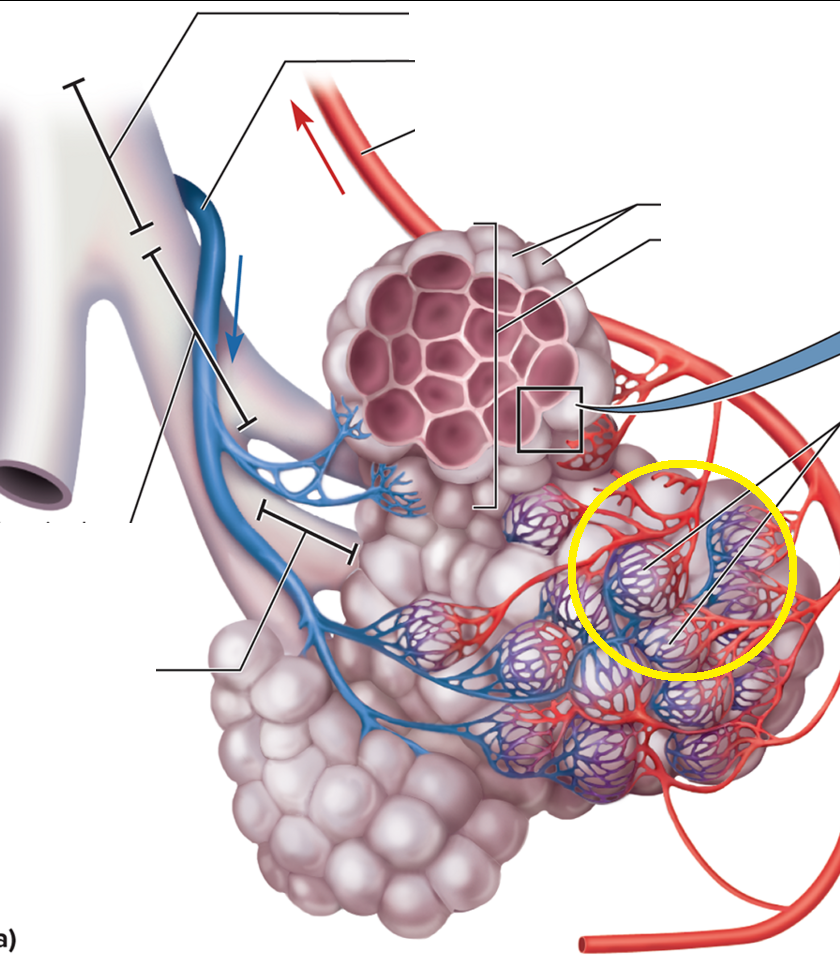

Trachea and Bronchial Tree

Carina T

Tracheal bifurcation T

Main bronchi BT

Lobar bronchi BT

Segmental bronchi BT

Bronchiole BT

Terminal bronchiole BT

resp bronchiole

Alveolar duct BT

Alveolar sac BT

Alveolus BT